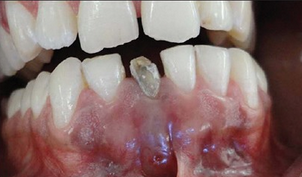

患者下前牙牙龈处溢脓,无疼痛感。患者幼时下前牙受过外伤,未治疗。

检查可见41牙大面积缺损,牙体变色,髓腔暴露,唇侧可见瘘道口。 X线片发现41牙根尖孔未完全形成,根尖周可见大面积低密度影,根中份可见有一高密度线性影像。仔细询问后发现患者有疼痛时往根管内放置尖锐物体的习惯。